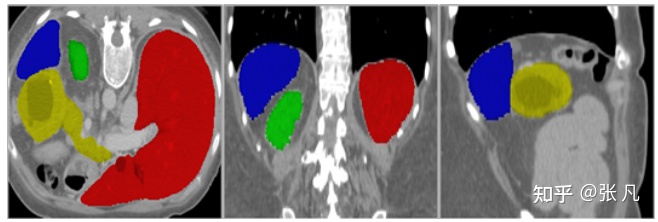

各个器官形状特征的分布如下。参考器官volume特征,设置保留最大连通区域的阈值;参考intensity特征,设置对比度增强参数;参考centroid_shift特征,统计器官之间的相对位置关系;参考axis_ratio特征,统计器官的形状差异。不同器官的大小符合正态分布;不同器官的相对位置是固定的;胰腺的形状差异较大。

badcase特征如下:

badcase主要包括器官病变和器官缺失,尤其是肾脏、肝脏病变case较多。

肾脏病变:

肝脏病变: